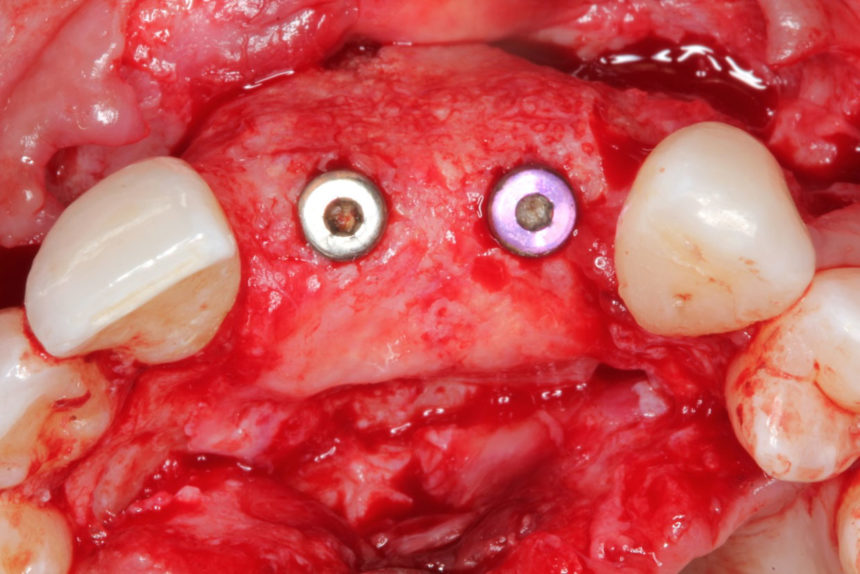

Οι συμμετέχοντες θα εξασκηθούν σε κάτω γνάθους χοίρων, με τα πιο σύγχρονα σχέδια εμφυτευμάτων, μικροχειρουργικά εργαλεία χειρός, bone tacks, βόεια υλικά πλήρωσης (filler) και απορροφήσιμες μεμβράνες και αυξητικούς παράγοντες με πλέγμα τιτανίου. Οι θεραπείες στις οποίες θα εκπαιδευτούν είναι:

1. Οριζόντια αύξηση ακρολοφίας με ταυτόχρονη τοποθέτηση εμφυτεύματος, τοποθέτηση οστικού μοσχεύματος σε στοιβάδες με απορροφήσιμη μεμβράνη & ράμματα στερέωσης

2.Οριζόντια αύξηση ακρολοφίας με τοποθέτηση απορροφήσιμης μεμβράνης, bone tacks & ανάμικτο οστικό Ξενο/Αυτο-μόσχευμα σε αναλογία 1:1